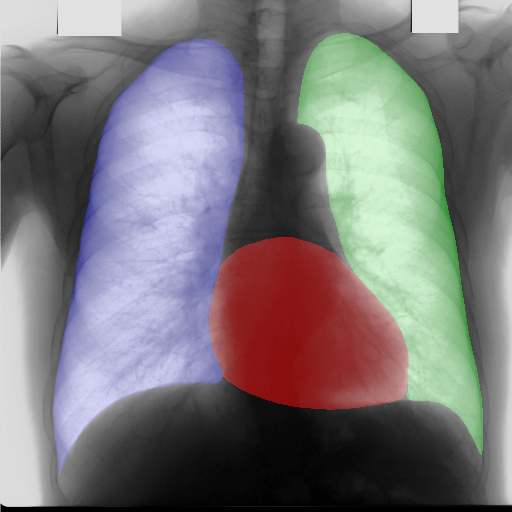

In this section, some examples of images and corresponding segmentations, generated with the approaches described in Section 3, are qualitatively examined. We also report some comments from three physicians on the generated segmentations, to provide a medical assessment of the quality of our method.

Figure 5 and Figure 6 display some examples — randomly chosen from all the generated images — of the label–maps and the corresponding chest X–ray images generated with the three methods described in Section 3, using the FULL_DATASET and the TINY_DATASET, respectively. We can observe that, with the single and two–stage methods, the images tend to be more similar to those belonging to the training set. For example, in most of the generated images there are white rectangles, which resemble those present in the training images, used to cover the names of both the patient and the hospital. Instead, the three–stage method does not produce such artifacts, suggesting that it is less prone to overfitting.

Moreover, in order to clarify the limits of the three–stage method, we assessed the quality of the segmentation results based on three human experts, who were asked to check 20 chest X–ray images, along with the corresponding supervision and the segmentation obtained by the SMANET network. Such images were chosen among those that can be considered difficult, at least based on the high error obtained by the segmentation algorithm. Figure 7 and Figure 8 show different examples of the images evaluated by the experts. The first column represents the chest X–ray image, while the second and the third columns, whose order was randomly exchanged during the presentation to the experts, represent the target segmentation and our prediction, respectively. The three physicians were asked to choose the best segmentation and to comment about their choice. Apart from a general agreement of all the doctors on the good quality of both the target segmentation and the segmentation provided by the three–stage method, surprisingly, they often chose the second one. For the examples in Figure 7, for instance, all the experts share the same opinion, preferring the segmentation obtained by the SMANET over the ground–truth segmentation. To report the results of the qualitative analysis, we numbered the target and predicted segmentation with 1 and 2, respectively, while doctors were assigned unordered pairs to obtain an unbiased result. Then, with respect to Figure 7(a), the comments reported by the experts were: 1) In segmentation 1, a fairly large part of the upper left ventricle is missing; 2) I choose the segmentation number 2 because the heart profile does not protrude to the left of the spine profile; 3) The best is No. 2, the other leaves out a piece of the left free edge of the heart, in the cranial area. Instead, for Figure 7(b), we obtained: 1) The second image is the best for the cardiac profile. For lung profiles, the second image is always better. The only flaw is that it leaks a bit on the right and left costophrenic sinuses. 2) Image 2 is the best, because the lower cardiac margin is lying down and does not protrude from the diaphragmatic dome. Image number 1 has a too flattened profile of the superior cardiac margin. 3) No. 2 for the cardiac profile more faithful to the real contours.